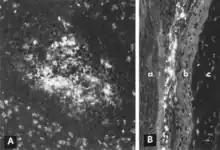

Acute infection of postnatal pigs, including pregnant dams that subsequently develop reproductive failure, is usually subclinical.[11][12][13][14][15][16] However, in young pigs and probably in older breeding stock as well, the virus replicates extensively and is found in many tissues and organs with a high mitotic index. Viral antigen is especially concentrated in lymphoid tissues[13][14] (Fig. 3A, B). Many pigs, irrespective of age or sex, have a transient, usually mild, leukopenia sometime within 10 days after initial exposure to the virus.[11][17][15][16] PPV and other structurally similar viruses have been identified in the feces of pigs with diarrhea.[18][19] However, there is no experimental evidence to suggest that PPV either replicates extensively in the intestinal crypt epithelium or causes enteric disease as do parvoviruses of several other species.[13][20] PPV also has been isolated from pigs with lesions described as vesiclelike. The causal role of PPV in such lesions has not been clearly defined.[21]

Replication of PPV in vitro is cytocidal and characterized by "rounding up," pyknosis, and lysis of cells (Fig. 1A). Many of the cell fragments often remain attached, eventually giving the affected culture a ragged appearance. Intranuclear inclusions develop[31] but they are often sparsely distributed.[39] Infected cultures may hemadsorb slightly[31] (Fig. 1B). Cytopathic changes are extensive when cell culture-adapted virus is propagated under appropriate conditions. However, on initial isolation several serial passages of the virus[31] or, better, the infected culture may be necessary before the effects are recognized. The use of immunofluorescence (IF) microscopy greatly increases the likelihood of detecting minimally infected cultures.[40][41]